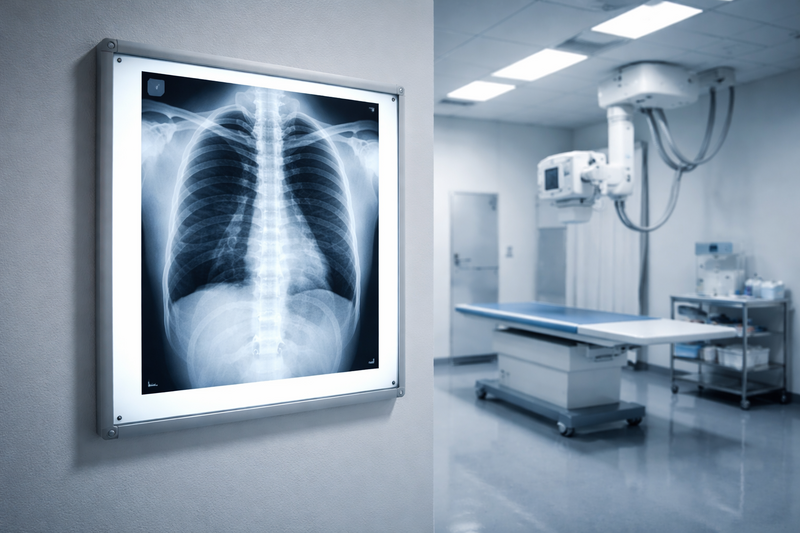

Рентгенография в медицине: принцип действия, показания и виды исследований

Саяногорск Инфо - Рентгенография в медицине: принцип действия, показания и виды исследований - rentgen.png

Рентгеновские лучи — это электромагнитное излучение с высокой проникающей способностью: проходя через тело пациента, они поглощаются тканями в разной степени. Плотные структуры — прежде всего костная ткань — задерживают излучение сильнее и дают светлые участки на снимке; воздухоносные полости, напротив, пропускают лучи практически без поглощения и отображаются тёмными зонами. Полученное изображение — рентгенограмма — фиксируется либо на специальной плёнке, либо на цифровом детекторе. Цифровой формат даёт ощутимые преимущества: снижение лучевой нагрузки, возможность мгновенной передачи данных и программного улучшения контраста без повторного облучения. Именно поэтому современные диагностические отделения — такие, как те, что проводят рентгенографию на цифровом оборудовании, — обеспечивают более высокую диагностическую точность при минимально возможной дозе.

• Органы грудной клетки — лёгкие, сердце, плевра и средостение; основной инструмент при пневмонии, туберкулёзе, плевральном выпоте и оценке сердечного контура.